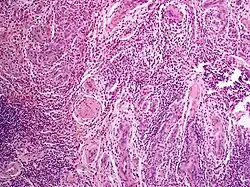

To make the diagnosis, a biopsy of the lesions is needed. Strong reactivity for CD31 and lower reactivity for CD34 and factor VIII-related antigen is shown by an immunohistochemical analysis.[18]

When angiolymphoid hyperplasia with eosinophilia lesions are examined under a microscope, a polymorphous vascular pattern made up of uniformly spaced linear and dotted vessels is visible over a background that ranges in color from pink to red.[19]